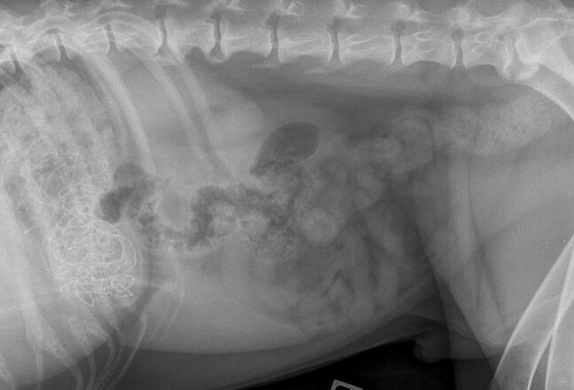

X光检查证实彩带在德克斯特的胃中,但是没有进入肠道,这极有可能会引起额外的并发症。